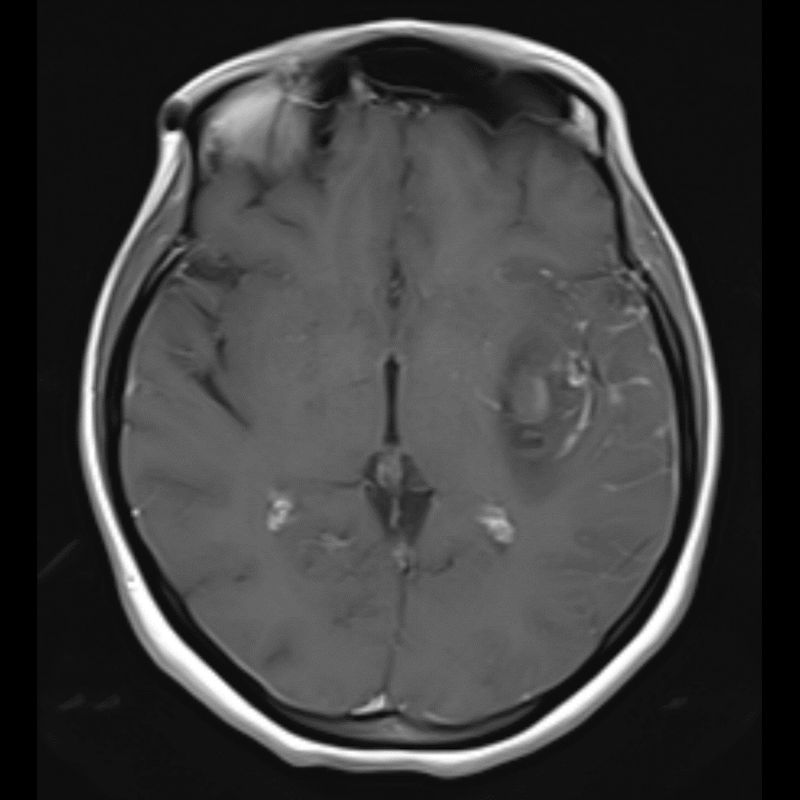

40 yaş, K

Ateş, bir haftadır artan baş ağrısı, yeni gelişen bilinç bulanıklığı

Sol MCA Segmet M2-3’te Sakküler Mikotik Anevrizma Rüptürü